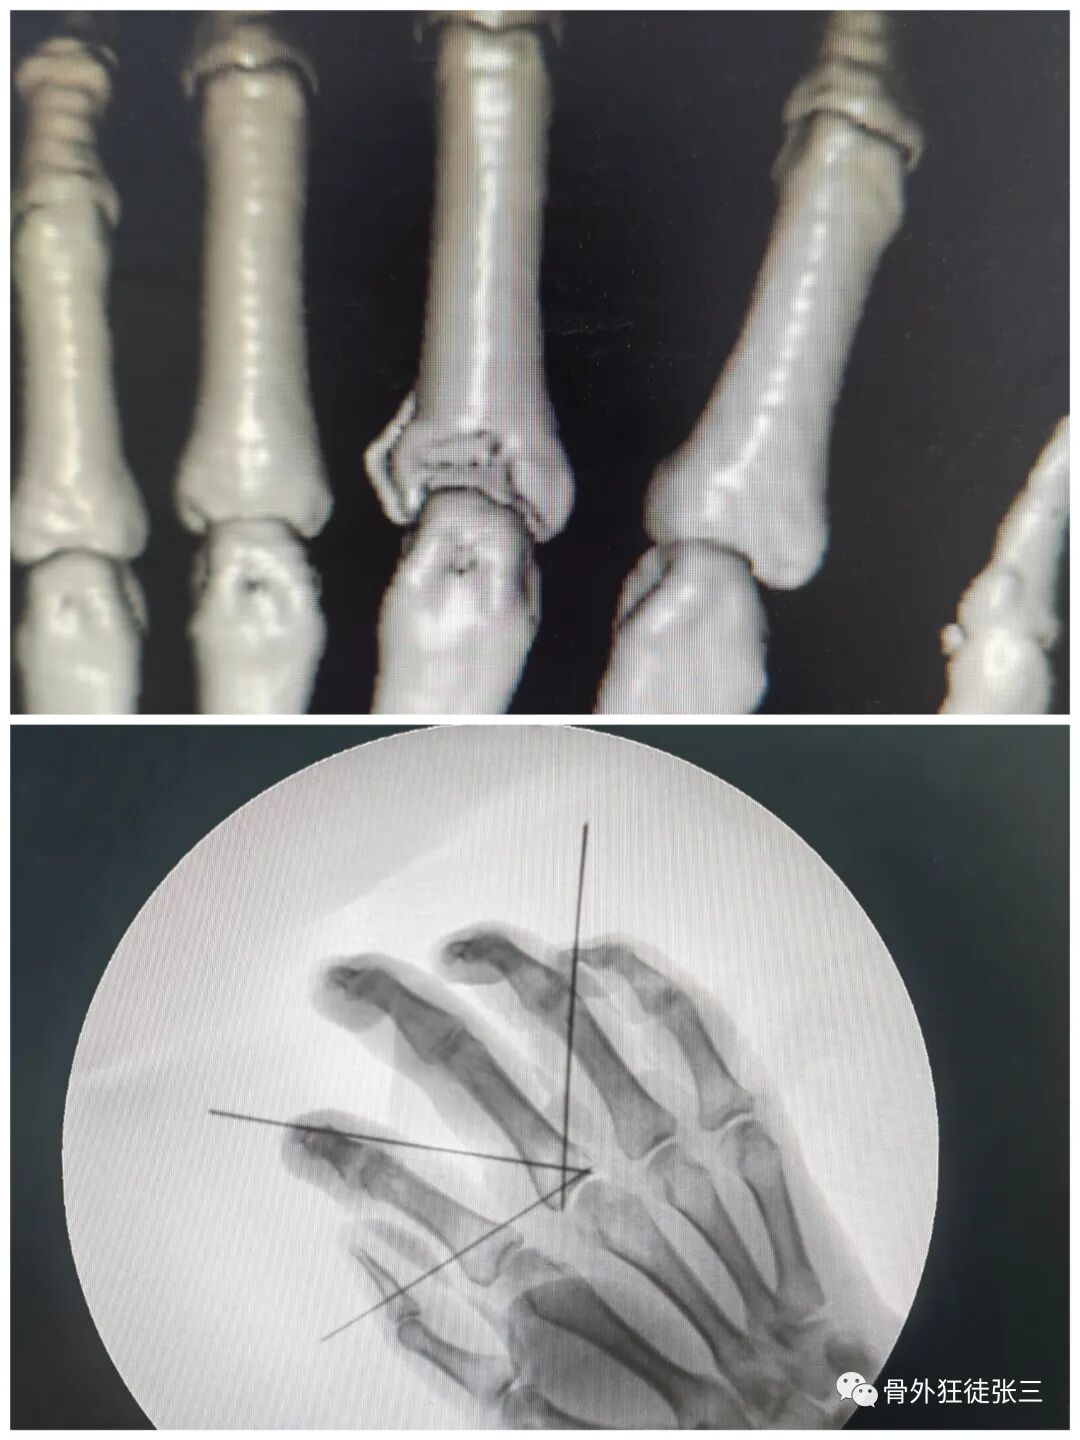

病例2,第4掌骨螺旋型骨折,经皮撬拔,克氏针支架。

病例5,开放性第3、4掌骨骨折,隔山打牛,克氏针支架。